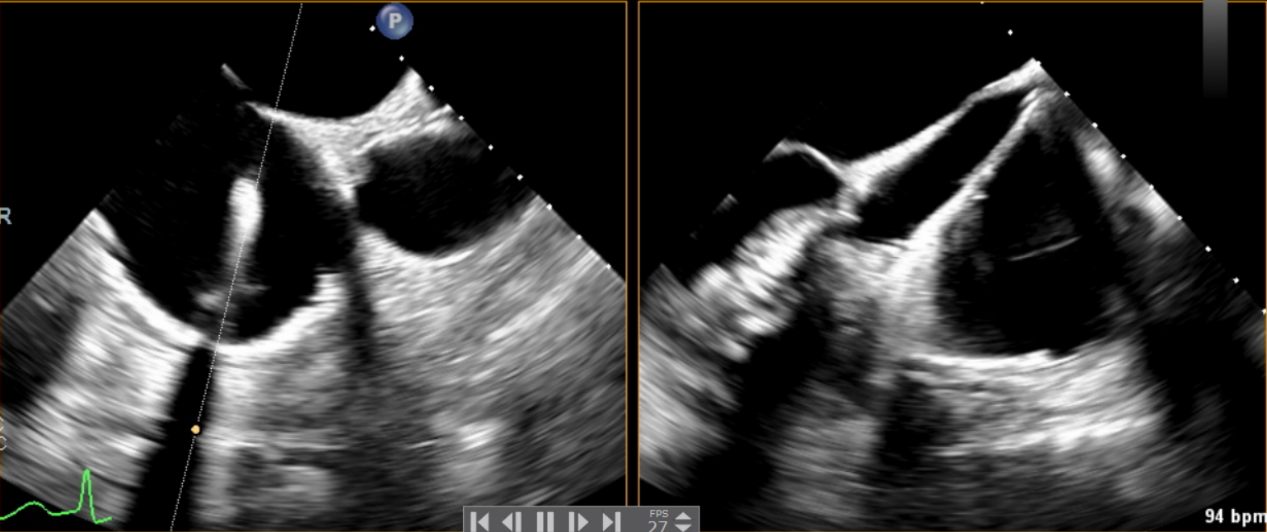

術中輸送器在超聲引導下調整位置

術后Azeem Latib教授對LuX-Valve Plus經血管三尖瓣置換系統的器械性能和治療效果大為稱贊,并且認為LuX-Valve Plus的手術體驗非常好。從治療效果來看,術后即刻超聲顯示三尖瓣反流幾乎完全消失,血流動力學改善顯著,患者恢復快。在面對復雜解剖結構、超聲影像質量不佳、有起搏導線干擾時,Lux-Valve Plus也體現了極強的適應性。Thomas Modine教授參與了術中指導,他同樣再次肯定了LuX-Valve Plus術中操作的便捷性,認為LuX-Valve Plus容錯率高,對術中影像的依賴小,并表達了后期希望可以更多地應用LuX-Valve Plus三尖瓣置換系統于臨床實踐,讓更多的三尖瓣重度反流患者盡早獲益,改善預后。